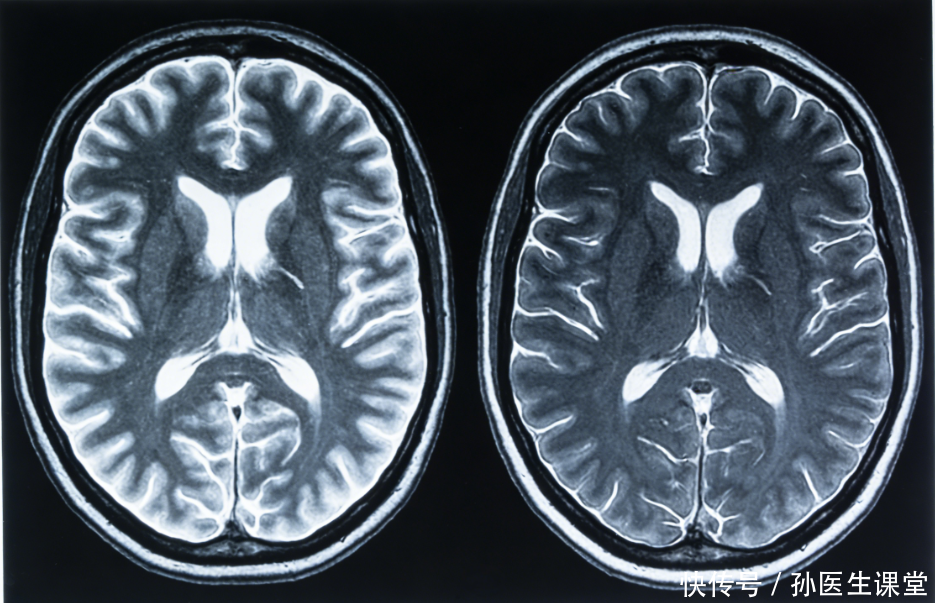

不同于大动脉堵塞引发的急性卒中,脑小血管病(CSVD)涉及的是颅内穿通动脉、小动脉及毛细血管。临床上,这类病变常在MRI检查中以形似满天星的“白质高信号”或微出血点呈现。这种微观层面的血管壁损伤,往往源于内皮细胞的长期炎症反应与血脑屏障的通透性改变。病变累积到一定阈值,执行功能下降、情绪抑郁及排尿障碍便接踵而至。它并非单一疾病,而是以腔隙性脑梗死、脑白质疏松为特征的一组病理综合征,隐蔽性导致其早期极易被忽视。